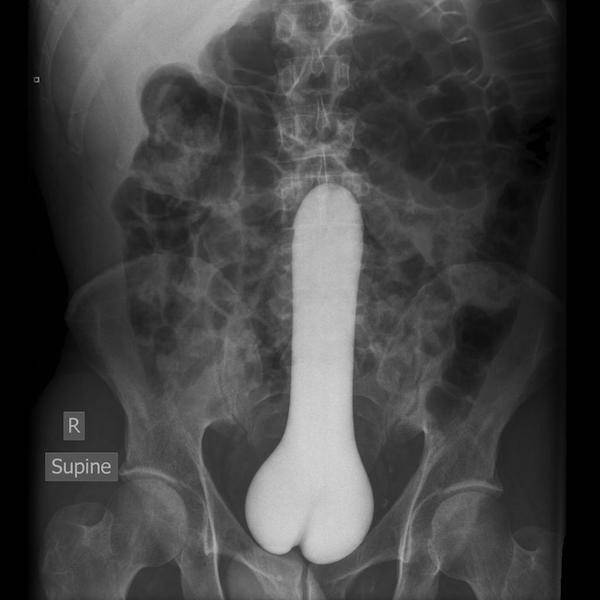

#19 Vibraattori